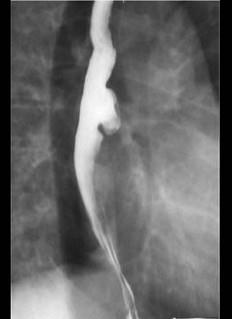

某患者因胸骨后不适行X线钡餐检查,结果如图所示,诊断为 ( )A、食管憩室B、贲门癌C、食管平滑肌瘤D、贲门失弛缓症E、食管癌

问题 某患者因胸骨后不适行X线钡餐检查,结果如图所示,诊断为 ( )

选项 A、食管憩室 B、贲门癌 C、食管平滑肌瘤 D、贲门失弛缓症 E、食管癌

答案 A